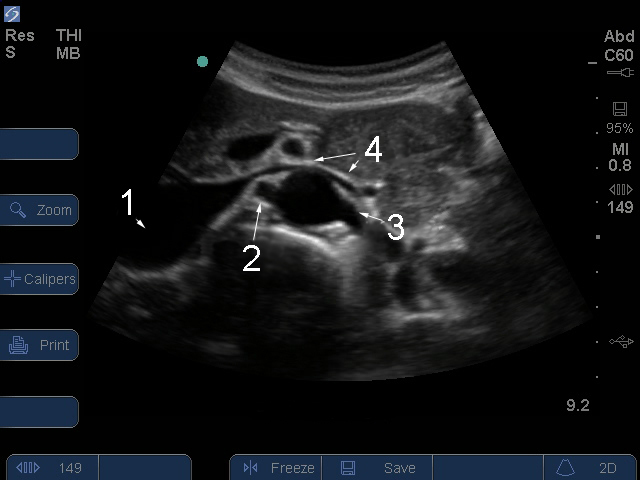

Orígenes de arteria renal

1. Vena cava inferior (VCI)

2. Arteria derecha

3. Arteria izquierda

4. Vena izquierda